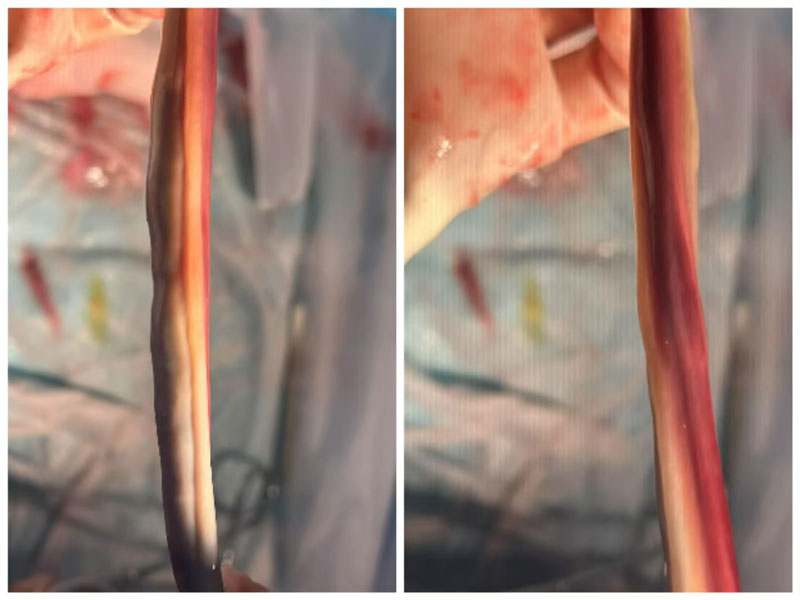

在產(chǎn)房,通過規(guī)范使用縮宮素促進(jìn)產(chǎn)程,母嬰平安誕下體重3250g的新生兒。產(chǎn)后證實(shí):存在單臍動脈伴另一動脈完全壞死。